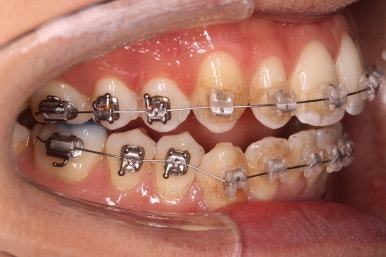

초진 시 입안의 모습입니다.

앞니가 약간 삐뚠 것 말고는 큰 문제는 없어보이네요.

장치를 부착했습니다.

이번 부산연제구교정 환자분이 선택한 장치는 엠파워 클리어라고 하는 자가결찰 세라믹 장치입니다.